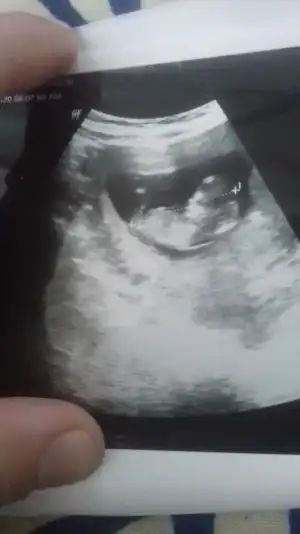

Merhabalar 😍 çok merak eden bu anne olarak arkadaşımın tavsiyesiyle sayfanızı gördüm rica etsem acaba bunuda yorumlar misiniz kız mı erkek mi acaba 😍 inşallah kizdir 😅 11+3 günlük bu ultrason resmi 😊 şimdiden teşekkür ederim ❤

Kız gibi sanki yinede 12+13 olursa paylaşın emin olamadım

Emin olamadım sanki kız gibi gibi 12+13 haftalarda paylasin